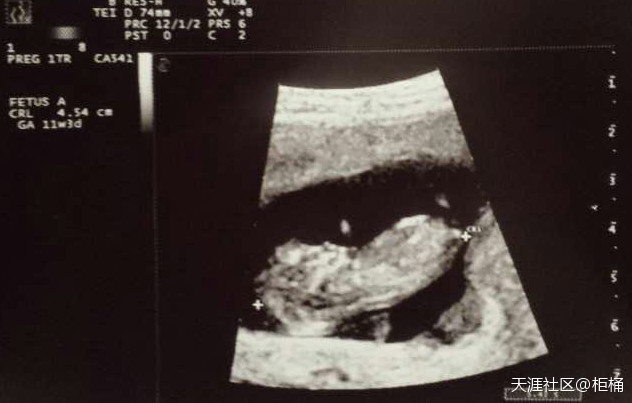

明天就满十一周了。这两个星期时不时的小腹会感到里面突然跳一下,位置不定,很像胎动的感觉。但以前都是起码十五六周才胎动的呀,有这么早就能感觉到的吗?不过胎儿现在这个孕周是确实会动的了,蹬腿什么的。我怀老二时十一周多去b超,就看见她在里面像青蛙似的不停蹬腿,不过那时候没感觉。

今天第一次去见产科医生,相当于国内的建卡了。简单b超了一下,看到小朋友在里面动手动脚的哈哈。本来我已经约了医院十月初做羊水穿刺,今天医生劝我去做母血查胎儿染色体那种检查,说会早点知道结果。我想也是,就马上去抽血了,两周后知道结果。这个检查在加拿大对四十岁以上孕妇免费。我就是不知道这个检查准确率高吗?我要不要还去做羊水穿刺呢?纠结啊!

从13周开始比较明显的感觉到胎动了,在里面轻轻的划一下。但胎动不频繁。好像这个宝宝比较懒,我12周去B超的时候,她在睡觉一动不动,用尽方法她才动了动两手。之前怀老二的时候,同样12周B超,看到她在里面像青蛙一样的拼命蹬腿啊,好搞笑。刚出生的时候洗完澡她也那样双腿一个劲的蹬,所以现在的腿比较粗壮,屁股也大,哈哈。